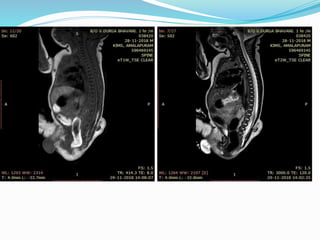

Caudal agenesis. T2 weighted sagittal (A), T1 weighted sagittal (B) and T2

weighted coronal (C) MR images showing type II caudal agenesis. There

is non-development of distal sacral vertebra with abnormal termination of

conus medullaris . The child also has associated left hydronephrosis